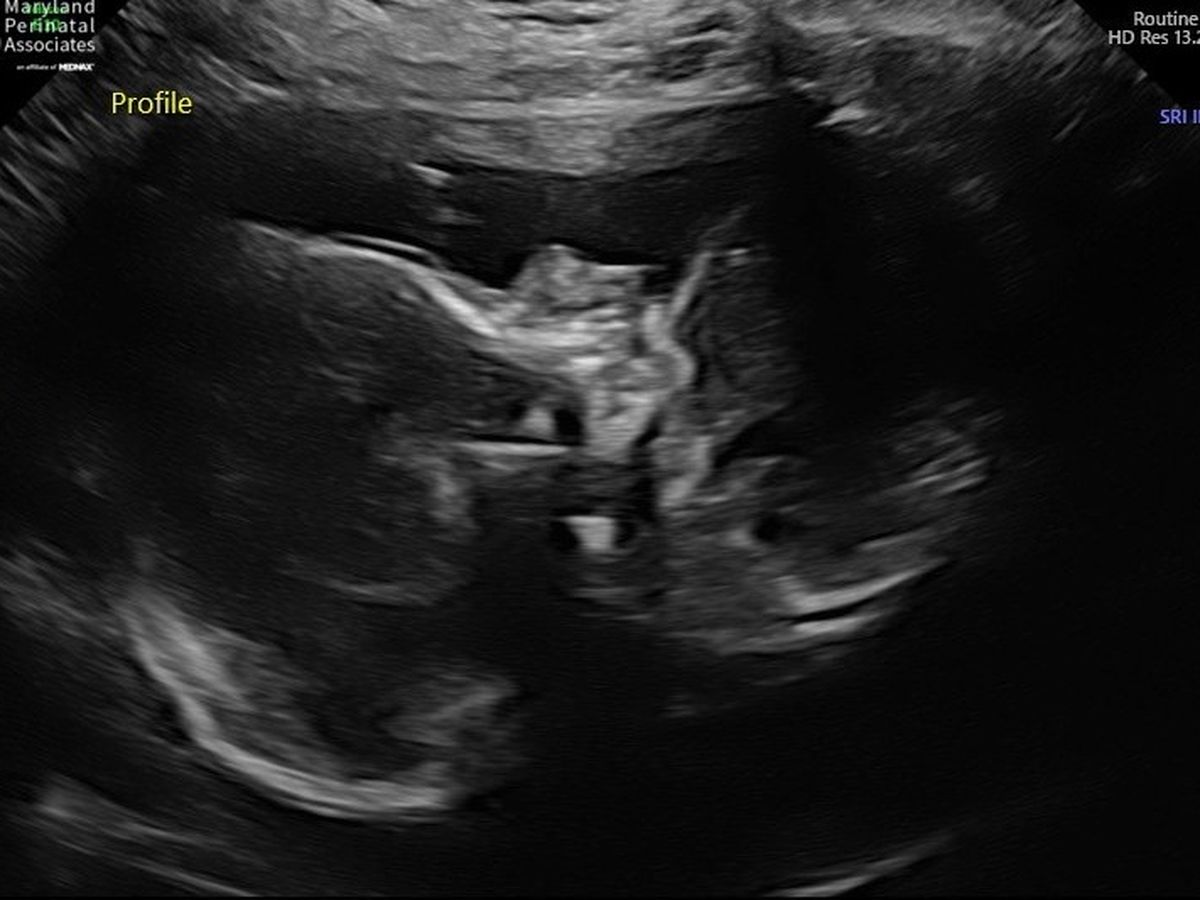

On Friday May 4th Shane and I went to our anatomy scan at 19weeks. They almost immediately stopped the scan and referred us to a high risk doctor. Brian was measuring 3 weeks behind (16wks). On Monday morning, we went to the high risk doctor where we learned that Brian was diagnosed with intrauterine growth restriction (IUGR). I was pulled out of work and placed on a high protein diet. They ran tons of blood work that all led to placenta insufficiency. Growth scans were then scheduled every 3 weeks. At the second growth scan at 22 weeks, Brian was now 4 weeks behind. Measuring 18 weeks and weighing about 8oz. At this point they have found restriction in the umbilical cord caused by the placenta insufficiency, low amniotic fluid, and now placenta previa. We were told to continue with protein shakes and to now add a low dose aspirin to our regimen. Today, June 15th I went for my routine OB appointment where I was sent over to my high risk doctor to have an emergency ultrasound done due to lack of movement. As of today, Brian is now measuring , 6 weeks behind. I am 25 weeks today but he is only the size of a 19 week old fetus. Weighing 10oz. Amniotic fluid is still pretty low and the placenta is really struggling at this point. We are waiting for our care to be transfered to University Of Maryland where they will eventually admit me and take Brian when they feel its necessary. In the meantime these scans are very expensive and are now needing to be done every week. The lab work is astronomical and the medical bill's are piling up. At this point, we don't know if baby Brian will make it but we will never give up hope. It is time that Shane and I ask for help. It's not what we want to do but it's getting hard to keep our heads above water at this time. If you can't help financially, we fully understand and just ask that you pray for our sweet boy. We will continue to update everyone, when we know more. Thank you so much for all of your help. Its appreciated far more then you will ever know. Please help us save our baby boy!